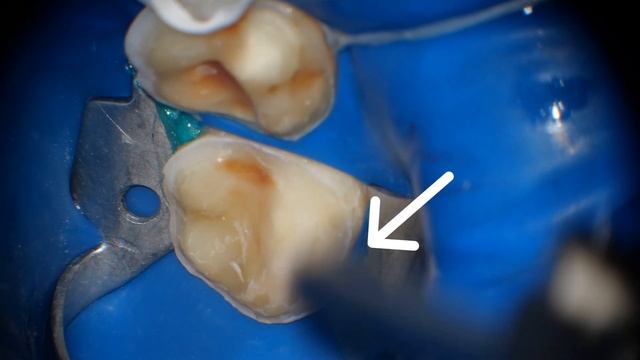

При работе с коффердамом часто именно в месте фиксации кламмера на молярах - подтекает слюна.

В этой ситуации удобно использовать жидкий коффердам и заполнить им место подтекания.

Но что делать если уступ находится низко в месте фиксации кламмера и туда не добраться жидким коффердамом? В таком случае можно использовать старый добрый слюноотсос поставив его под коффердам возле нужного зуба. Мы в соц.